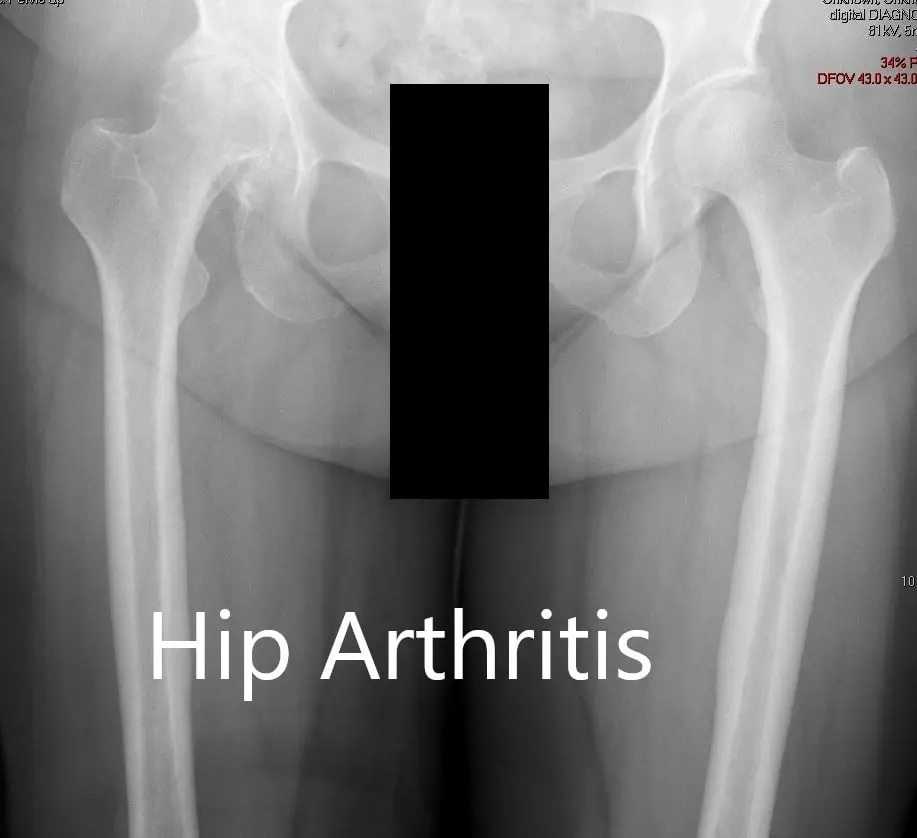

There was no distal neurological deficit. The distal extremity pulses were good volume and palpable. There was a linear scar over the right knee consistent with a previous right knee replacement. Imaging studies revealed severe osteoarthritis of the right hip.

Preoperative X-ray showing the AP view of the pelvis with both hip joints